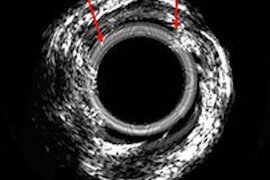

Photoacoustic radar offers route to spotting arterial plaque

University of Toronto develops dual-wavelength variant of PA radar technique.